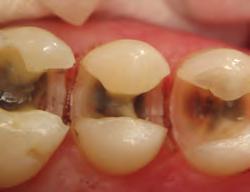

• Stains carious and demineralized dentin

Sable Seek caries indicator contains FD&C dyes, and Seek caries indicator contains D&C dyes in a glycol base. Both are used to stain carious and demineralized dentin.

Seek and Sable Seek caries indicators stain carious and demineralized dentin and can be very useful for difficult-to-see areas, for example; undercuts of preparations, dark dentin, areas along the DE junction, etc. Green Sable Seek caries indicator helps visualization of decay in deep caries cases to help avoid pulp exposures.